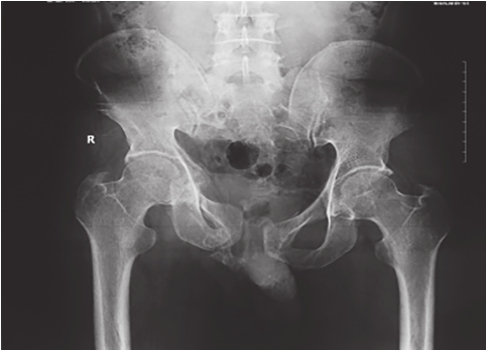

在压缩型损伤中,骨盆后环损伤侧的髂骨翼向内旋,在X线正位片中,其髂骨翼宽度(测量髋臼上方髋骨或骶髂关节至髂前上棘之间距离)比对侧窄。由于髂骨扭转,其闭孔由斜变正,显得大于对侧,耻骨联合被挤离中线,向对侧移位。伤侧髂骨向上脱位或移位多者可造成耻骨联合上下分离。在分离型损伤中,后环伤侧髂骨翼向外旋,由斜变平,显像宽于对侧,耻骨联合被牵拉离开中线向伤侧移位,或出现耻骨联合分离,外旋髂骨的闭孔更斜,故显像比对侧小。此类骨折损伤严重,常合并休克,手术时需要前后联合入路(图2-10)。

图2-10 骨盆扭转变形X线片

可见右侧耻骨上、下支骨折,耻骨联合分离,右侧骨盆向上移位,提示右侧骨盆后环损伤,向外旋转变形。